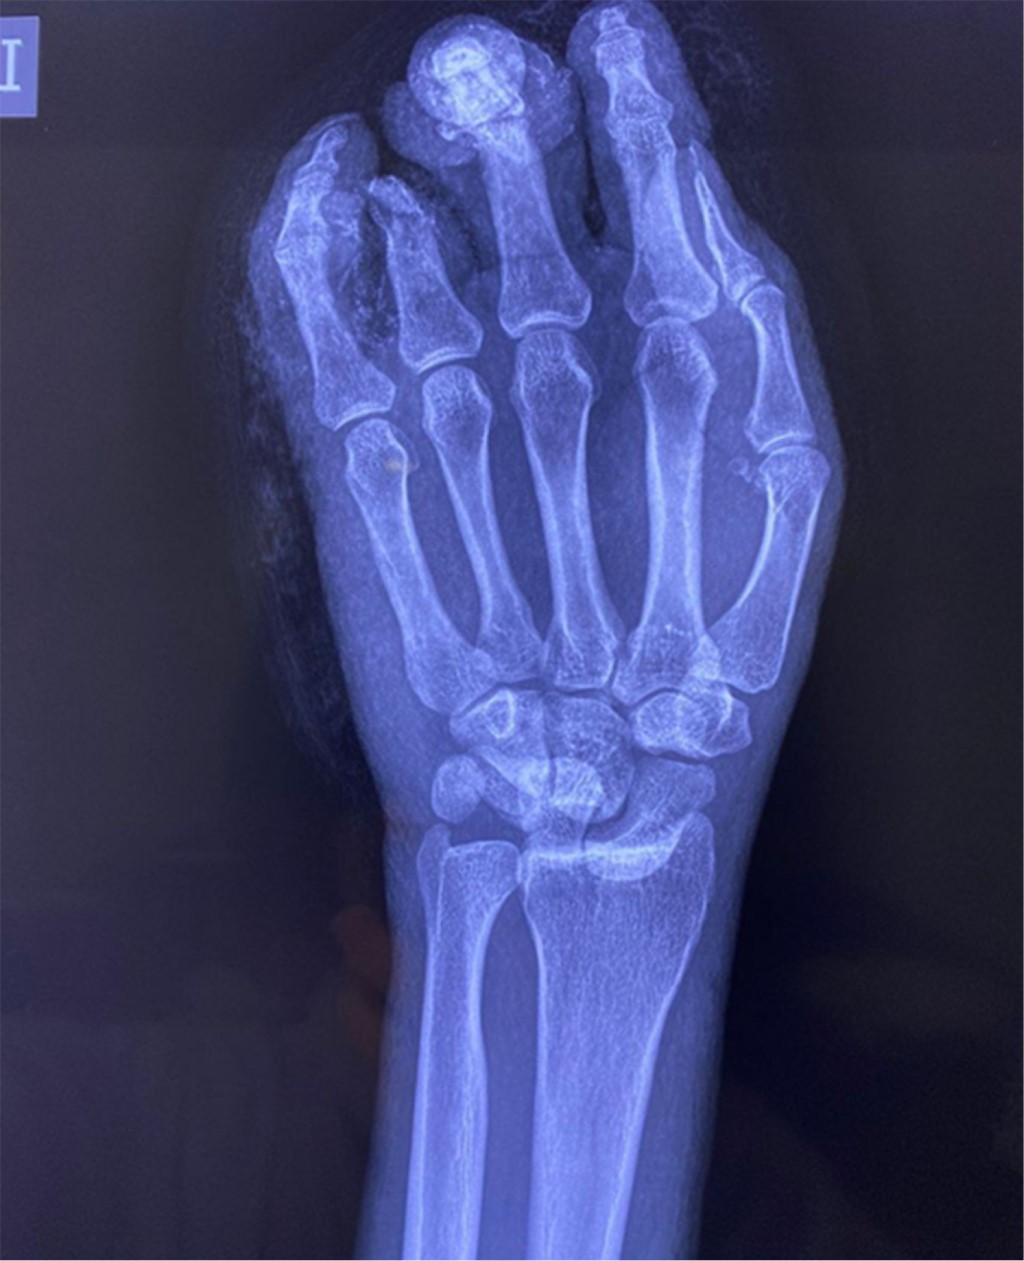

Además de presentar fractura en metáfisis proximal con extensión a metáfisis distal de F2 de tercer dedo, amputación traumática con desarticulación de F1-F2 más denudamiento de cuarto dedo, herida cruenta de quinto dedo más lesión del extensor propio del quinto dedo en zona V. A su ingreso pasa a cirugía de control de daños más reducción cerrada de luxación peri-escafo-transtrapecio-transtrapezoidea (Figura 3).

Durante su estancia se manejó con impregnación antibiótica más analgesia; posterior a la impregnación antibiótica, pasa a procedimiento definitivo donde se realizó carpectomía de muñeca izquierda (Figuras 4 y 5) con artrodesis de articulación interfalángica de F2-F3 tercer dedo (Figura 6) más tenorrafia de extensor propio de quinto dedo (Figura 7) y colgajo de herida cruenta en quinto dedo (Figura 8).